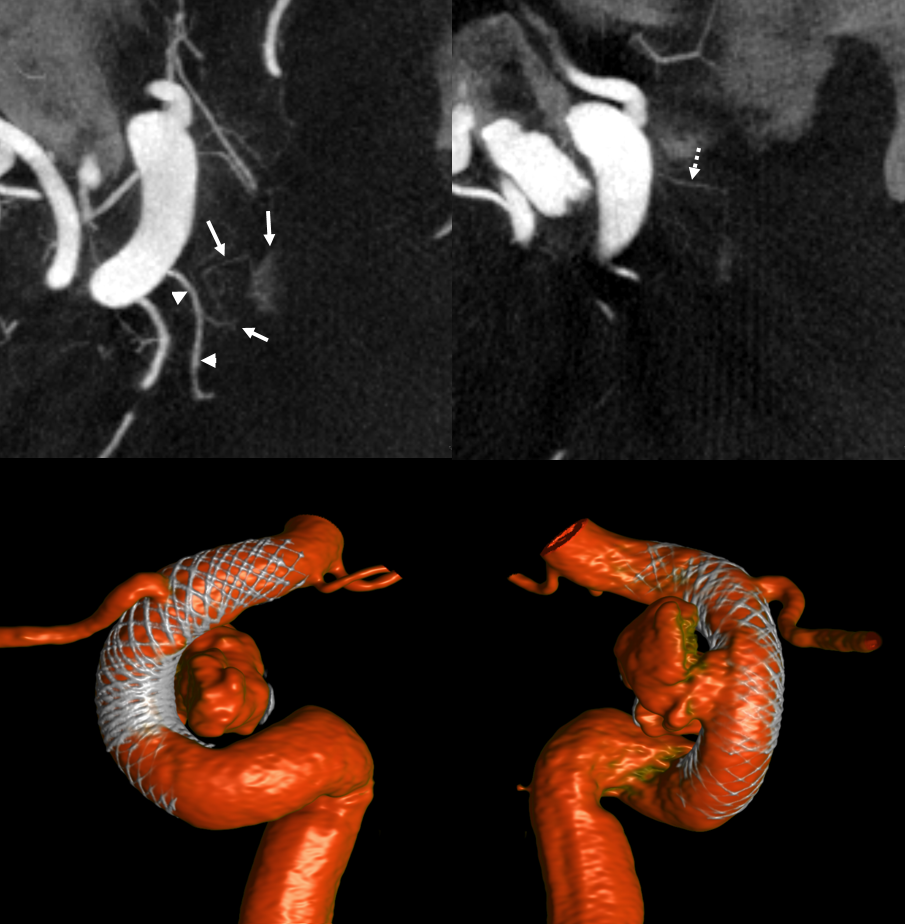

Case courtesy Dr. Eytan Raz — here is a beautiful example of a very dominant superior hypophyseal artery (arrow) supplying the posterior hypophysis (arrowhead), with a correspondingly small inferior hypophyseal contribution from the MHT (dashed arrow)

Cross eye stereo

View from the back — again small inferior hypophyseal, big superior hypophyseal — balance again… See the beautiful vascular ring of the posterior pituitary — the connecting it with the contralateral side

Cross-eye stereo

MIP image shows the sella nicely — and helps prove its posterior pituitary

Pure arrowless images — easier to steal…

Of course, there is an aneurysm here — the branch point camp would point out how this larger than usual branch is a setup for aneurysmal formation. Naturally…